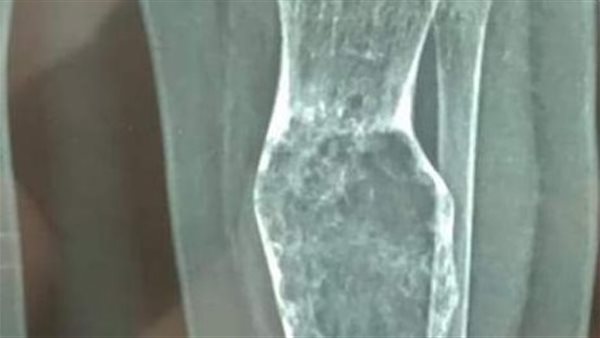

أعلنت الهيئة العامة للرعاية الصحية، نجاح قسم جراحة أورام العظام بمنظومة التأمين الصحي الشامل بمحافظة بورسعيد، من إجراء تدخل جراحي ناجح لرضيع يبلغ من العمر 9 أشهر، بواسطة جهاز الحفار عالي السرعة.

قام الفريق الطبي، بإجراء كحت لكيس ورمي لعظمة القصبة، وتم أخذ عينة منه وتنظيف الأنسجة الورمية داخل الكيس العظمي، مع المتابعة الدورية بواسطة جهاز الحفار عالي السرعة، وذلك داخل غرف عمليات المبرة.